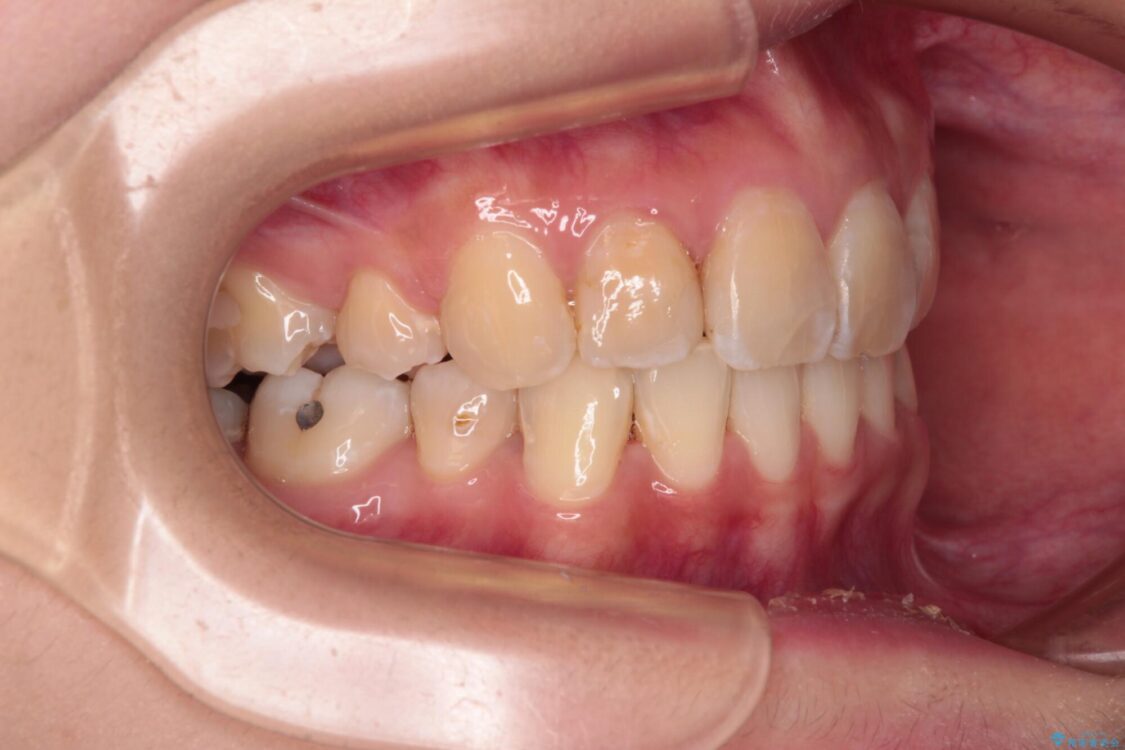

内側に倒れ込んだ歯や下の前歯が隠れてしまうほどの咬み合わせを改善したいとのことで来院された患者様です。

治療前

• デコボコと深い咬み合わせ ワイヤー装置での抜歯矯正 治療前画像